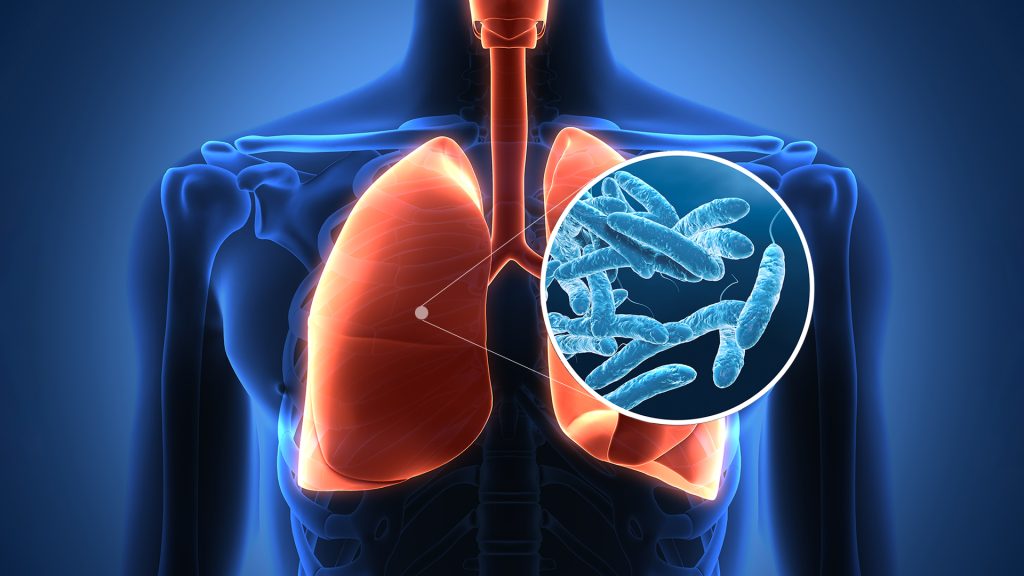

يذكر أن مرض الفيالقة هو نوع من الالتهاب الرئوي الذي تسببه بكتيريا الفيلقيات، التي تنمو في المياه الدافئة وتنتشر من خلال أنظمة المياه في المباني. وقد تم ربط تفشي المرض في المدينة بأبراج التبريد، التي تستخدم الماء ومراوح لتبريد المباني.

وعادة ما يصاب الناس بالأعراض وهي السعال والحمى والصداع وألم العضلات وضيق التنفس خلال فترة تتراوح بين يومين وأسبوعين بعد التعرض للبكتيريا، وفقا للمراكز الأميركية للسيطرة على الأمراض والوقاية منها.